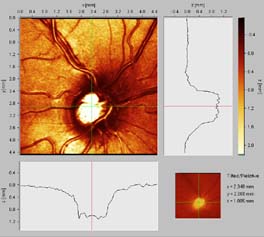

Vrstva nervových vláken

Je tvořena axony gangliových buněk pokrytých astrocyty, probíhajících v kanálcích z výběžků Mullerových buněk ve svazečcích o průměru 20 um. Svazečky jsou morfologickým podkladem jemného žíhání. Světlé proužky mezi tmavými mezerami jsou výběžky Mullerových buněk, ve kterých probíhají nervová vlákna. Temporálně i nasálně je žíhání jemné a každý proužek je tvořen jedním svazečkem vláken. V horním i dolním temporálním kvadrantu je jsou proužky silnější a tím i lépe viditelné, každý proužek má několik svazečků (svazečky jsou v několika vrstvách).

Při progresi glaukomu nejprve bývají poškozeny gangliové buňky v blízkosti temporálního švu sítnice. Jejich axony probíhají v hlubší vrstvě nervových vláken a do zrakového nervu pronikají v jeho periferii. Protože vzniklý defekt je překryt dalšími povrchnějšími vrstvami, výpadek není při pozorování sítnice zřetelný. Až po ztrátě poloviny vrstvy nervových vláken se defekt stává zřetelným oftalmoskopicky.

Technika vyšetření vrstvy nervových vláken

Pomůcky: štěrbinová lampa, 90 D čočka a fixační světélko na protější straně místnosti.

Nastavení lampy: zelené světlo paralelně s osou našeho pohledu, paprsek co nejvíce vertikálně protažený, aby pokryl oblast horních i dolním temporálních nervových svazečků. Zaostříme na terč tak, abychom ho viděli prostorově.

Pohybem štěrbinové lampy pak světelný proužek posuneme mezi terč a foveolou. Pohledem srovnáváme žíhání sítnice směrem dovnitř od velkých cévních kmenů, srovnáváme rozdíl mezi horními a dolními svazky vláken. U zdravého oka bývá žíhání a zastření cévních kmenů směřujících do makuly výraznější v dolní polovině sítnice než v horní.